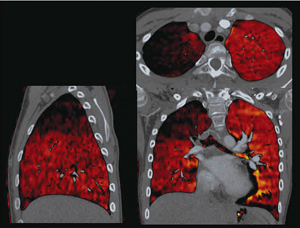

当院では,SOMATOM Definition Flashを用いて,ルーチンでの冠動脈解析やステント留置術後のフォローアップはもちろん,Flash Spiralなどの高速撮影による小児先天性心疾患の診断や,術後の肺野の血流確認のためのDual Energy ImagingによるLung PBVなどを行っている(図1)。そのため,ルーチンの冠動脈解析は,なるべく少ない負担で迅速な処理が求められる。

図1 Dual Energy Lung PBV